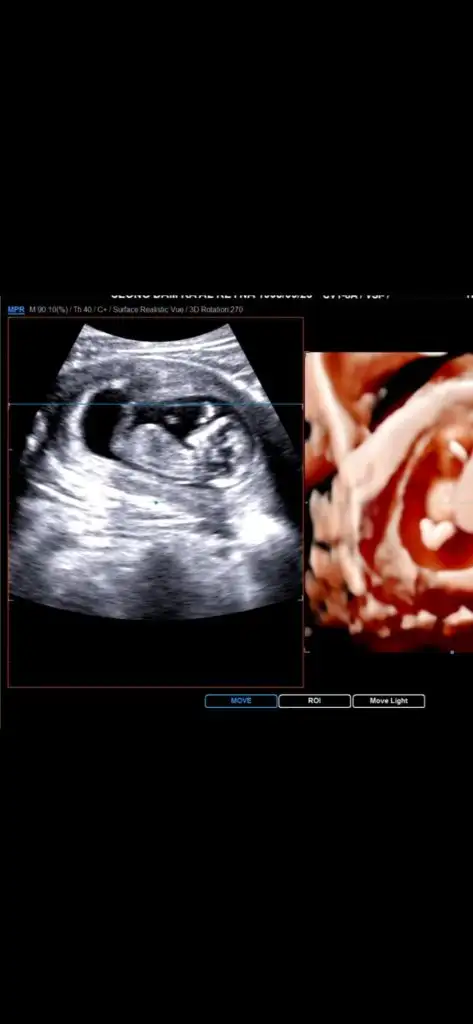

Evet benim idrar cikti doktorum da panikledi resmi atiyim bakinÇok geçmiş olsun canım. Gelen sıvı idrar olabilirmi peki. Geçen bir arkadaşında öyle olduya, su geldi diye paniklemişti ama idrar kaçırmış aslında.